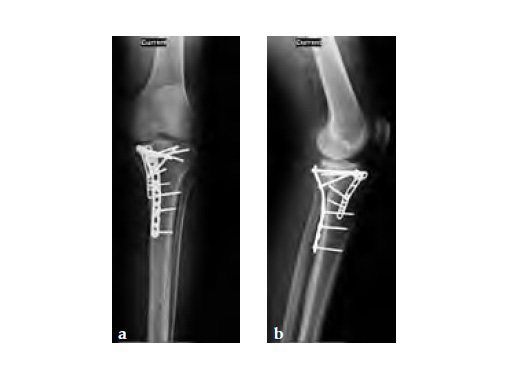

A 33-year-old male was involved in an altercation and suffered a gun shoot wound to his knee

Case provided by Brent Norris, Tulsa, USA.

Initially taken for incision and drainage and then ORIF . Patient placed in a floppy lateral position with the effected lower extremity externally rotated (opposite hip and shoulder bumped up about 3040) allowing exposure of the posterior medial knee. A posterior medial and an anteromedial incision were used to repair the fracture with a 67 cm skin bridge.

Postoperative healing was uneventful and the patient had no complications.